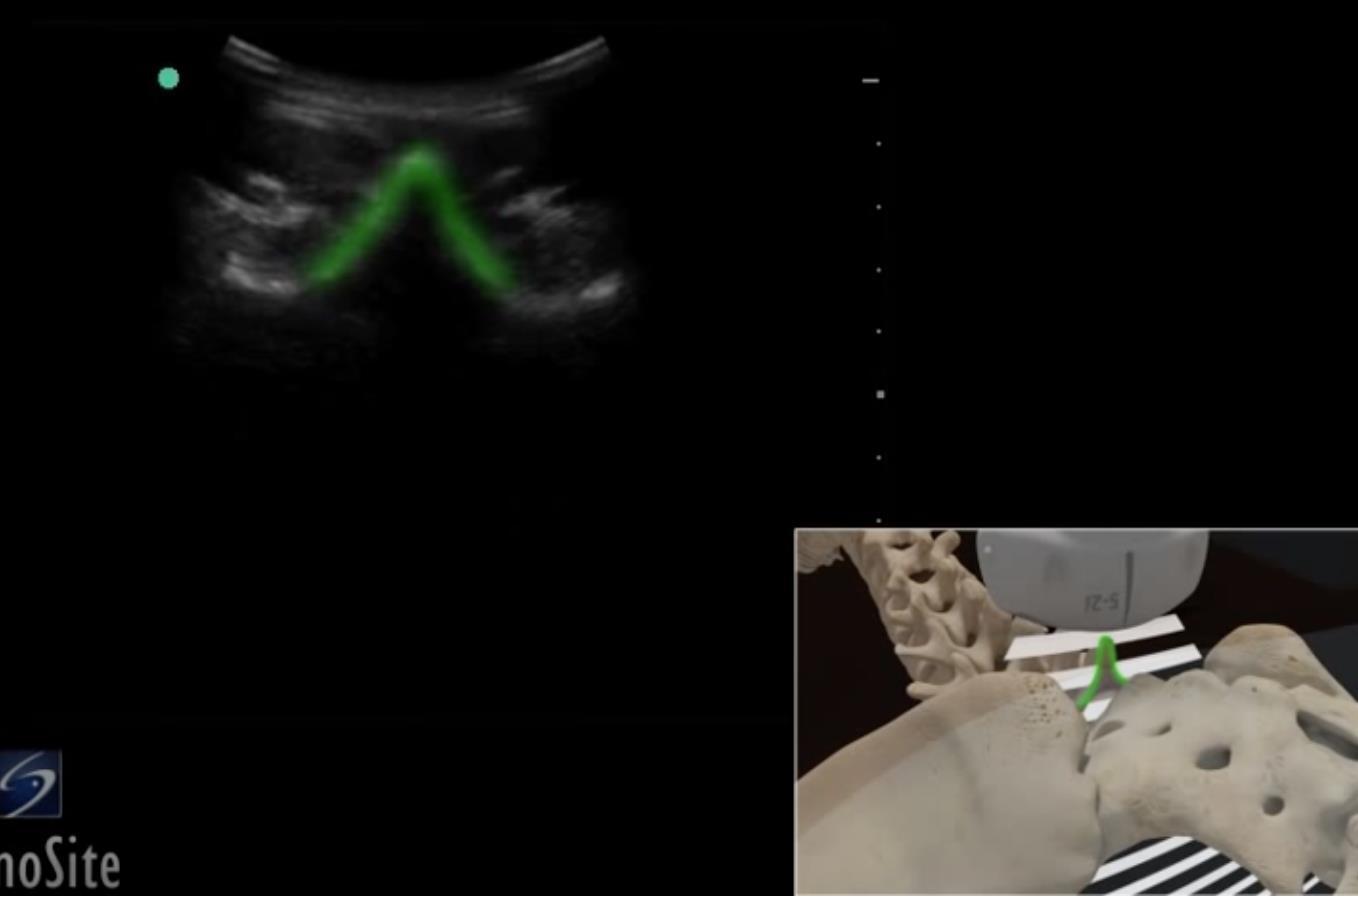

Cadera - Apófisis espinosa lumbar - Imagen

Área resaltada: Apófisis espinosa lumbar